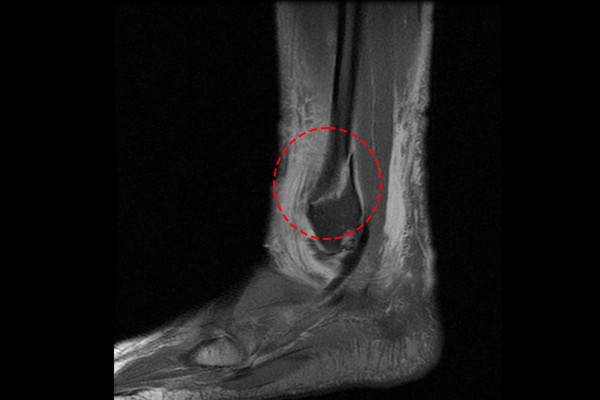

주변 인대손상 및 힘줄손상의 가능성도 있기 때문에 좀 더 자세한 확인을 위해 MRI 촬영을 진행한 결과, MRI에서도 역시 발목 외측 복숭아뼈(복사뼈) 골절이 확인되어 좌측 발목 외복사 골절(Lt. ankle lateral malleolar Fx.)을 진단하였습니다.